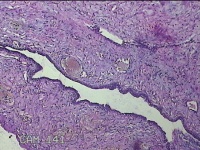

右侧卵巢囊肿

性别

女

年龄

36岁

临床诊断

一般病史

发现双侧附件囊肿1年。

标本名称

大体所见

灰白暗红色囊壁样组织2.5x2x0.3cm一块,表面光滑,部分已切开,囊内容物已流失,囊壁厚0.2cm。

考虑:子宫内膜异位囊肿。